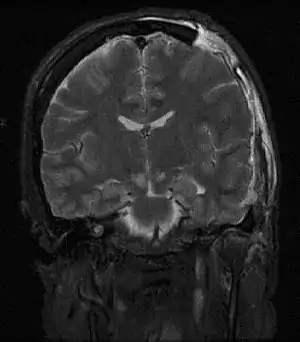

| امآرآی آسیبی را که هرنی مغزی وارد ساخته، نشان میدهد. | |